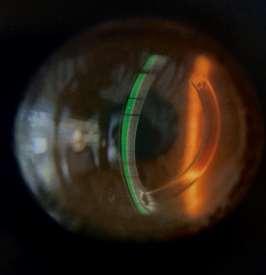

Figura 12. Aspecto del clearance de ojo derecho e izquierdo respectivamente, inmediatamente después de colocar loslentes miniesclerales OneFit de prueba en ambos ojos.

Al adaptar lentes de contacto de apoyo escleral, es indispensable esperar el asentamiento escleral del lente durante aproximadamente dos horas, considerando que este se “entierra” sobre el tejido conjuntival y episcleral antes de tomar su posicionamiento definitivo, con lo cual se evalúa su adaptación real y se descartan futuros problemas de sensibilidad o funcionalidad en el paciente.

Figura 13.Clearance formado por loslentesminiescleralesOneFit, tras unahora de “asentamiento” o uso continuo, tanto en ojo derecho como izquierdo en forma respectiva.

La evaluación biomicroscópica del lente mini escleral OneFit, revela una disminución del clearance especialmente inferior-, y genera un peligroso acercamiento al anillo implantado que puede afectar la comodidad y la fisiología corneal. Para corregir esto, se reduce la curva base para aumentar la profundidad de la bóveda sagital en 200 micras, y se opta por un perfil oblato del ápice del lente para acercar su cara posterior al centro corneal, con lo que se reduce el clearance central en esta zona, se provee mayor comodidad, y se minimiza la sobrecorrección negativa por compensación del menisco lagrimal; una vez transcurrido el tiempo de asentamiento del lente se procedió a evaluar la sobrerrefracción final y la zona periférica, como sigue a continuación: